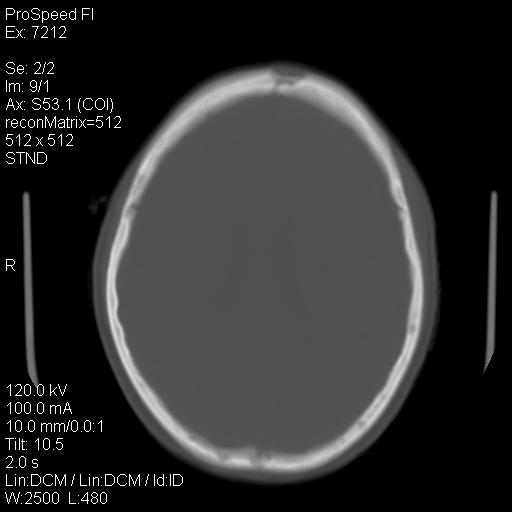

右额叶脑沟变浅,脑表面见新月形稍高密度影,考虑慢性硬膜下出血可能。

额顶骨多发穿凿样骨缺损区,不排除骨髓瘤等改变,进一步检查。

1)右侧半卵圆中心腔隙性脑梗塞。2)考虑左侧额部慢性硬膜下血肿(或硬膜下积液)。3)颅骨骨髓瘤不排除;建议行进一步检查。